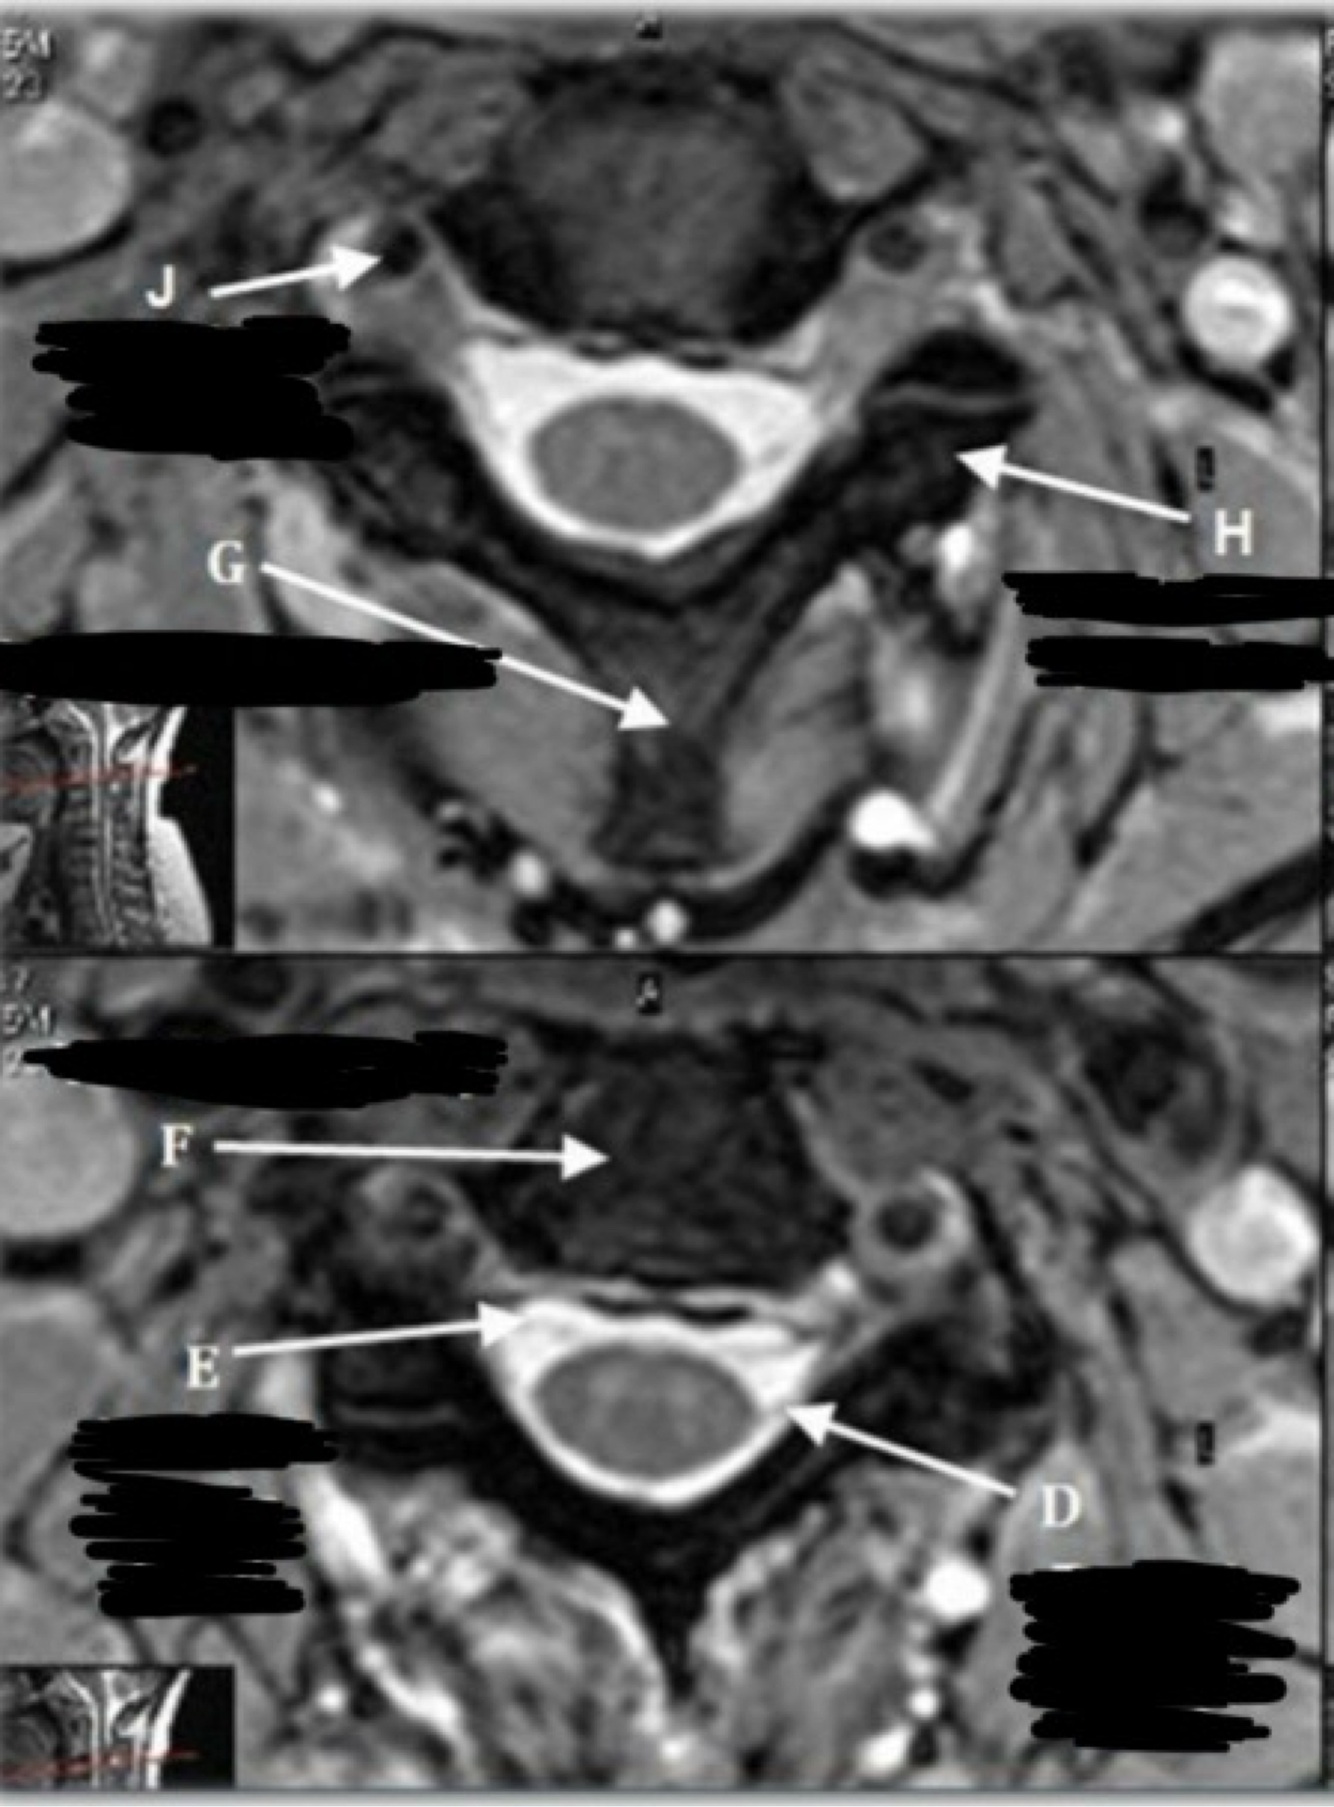

7

What is letter G?

A

8

What is letter H?

POSTERIOR LONGITUDINAL LIGAMENT (PLL)

9

What is letter J?

ANTERIOR LONGITUDINAL LIGAMENT (ALL)

16

SPINOUS PROCESS

17

TRANSVERSE PROCESS

18

VERTEBRAL ARTERY